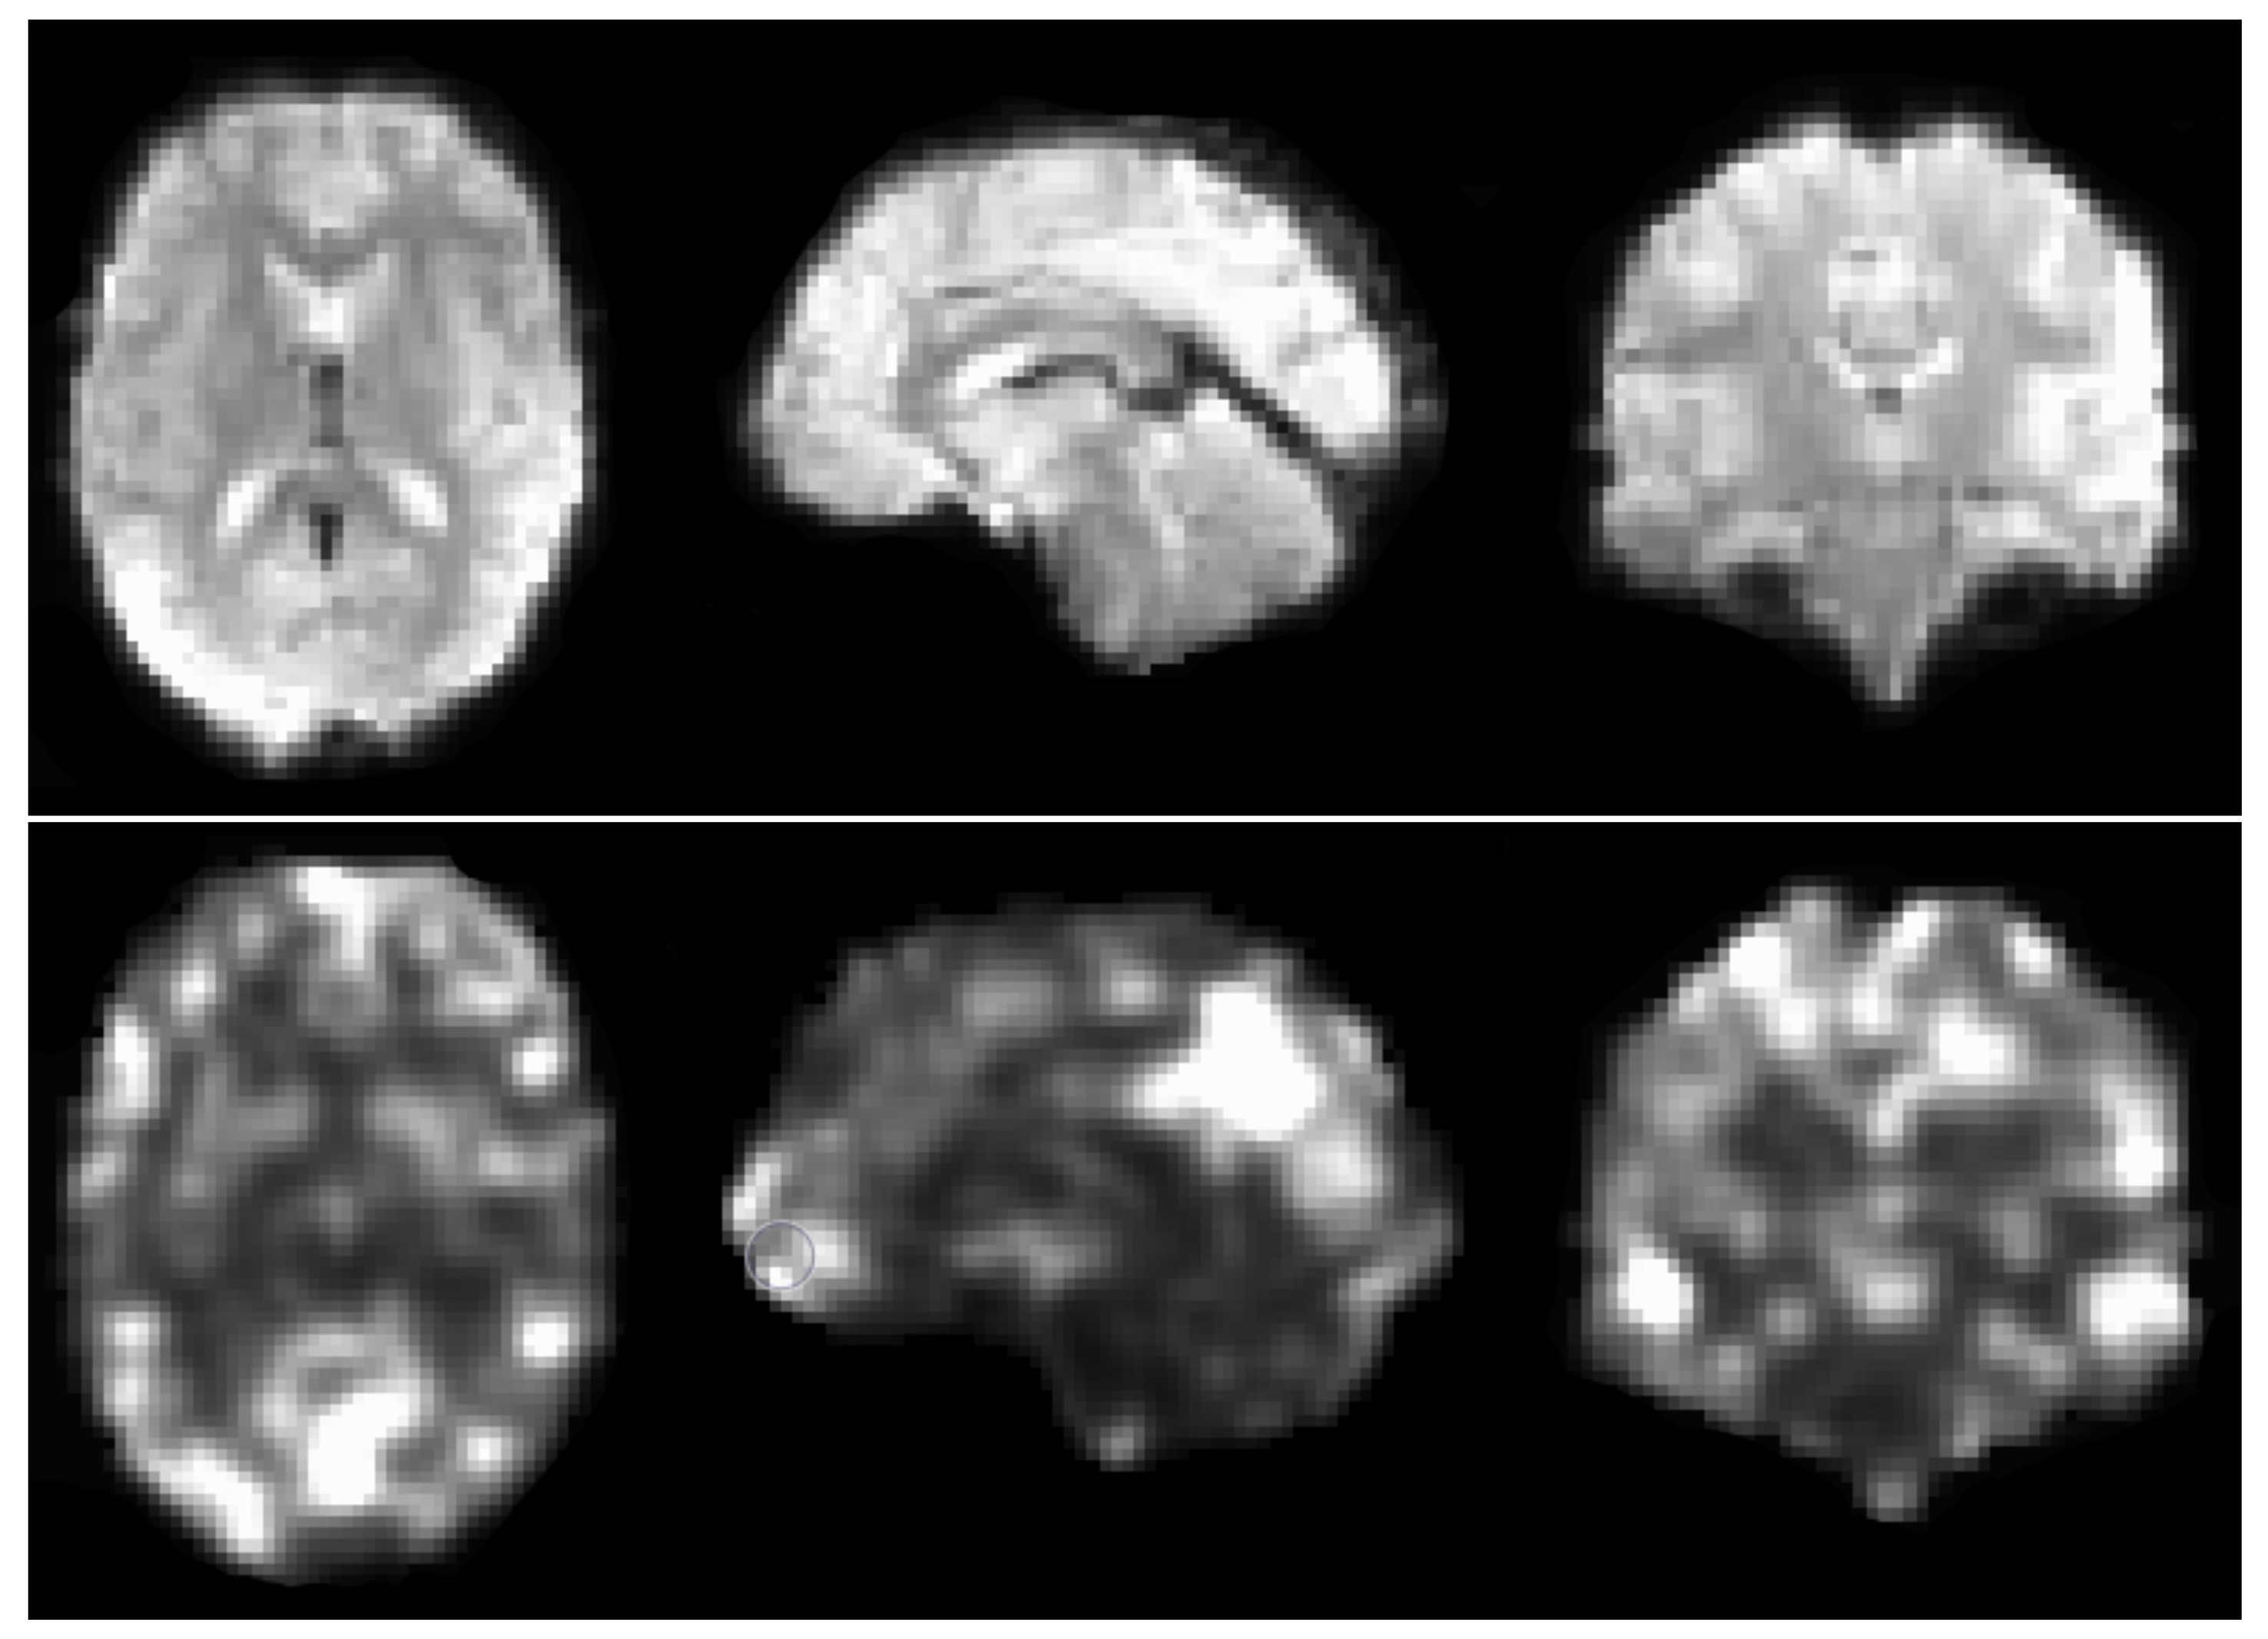

After preliminary testing of the 10 available derivatives available in ABIDE preprocessed (amplitude of low frequency fluctuations (ALFF), weighted and binarized degree centrality, dual regression, weighted and binarized eigenvector centrality, fractional ALFF, local functional connectivity density (LFCD), regional homogeneity (REHO), voxel-mirrored homotopic connectivity (VMHC)), the REHO derivative was chosen for comparing different augmentation strategies. Regional homogeneity is a measure of correlation between a voxel’s time series and those of its neighbours [36], based on the non-parametric rank correlation statistic known as Kendall’s Coefficient of Concordance (KCC) [37]. Each derivative volume from the resting state fMRI data has a size of 61 × 73 × 61 voxels (each 3 × 3 × 3 mm 3 ), which is fed into the 3D CNN described below. See Figure 1 for a preprocessed fMRI volume and the REHO derivative from the CCS pipeline, downloaded from ABIDE (https://s3.amazonaws.com/fcp-indi/data/Projects/ABIDE_Initiative/Outputs/ccs/filt_global/func_preproc/OHSU_0050147_func_preproc.nii.gz, accessed on 1 August 2023; https://s3.amazonaws.com/fcp-indi/data/Projects/ABIDE_Initiative/Outputs/ccs/filt_global/reho/OHSU_0050147_reho.nii.gz, accessed on 1 August 2023). The 539 subjects with ASD and the 573 controls were split 70/15/15 into training, validation, and test sets.

Figure 1. (Top): an fMRI volume obtained after preprocessing with the CCS pipeline. (Bottom): the REHO derivative obtained from the preprocessed 4D fMRI dataset, used by the 3D CNN to classify each subject as control or ASD. Different types of 3D augmentation were applied to each REHO volume, in an attempt to improve the test accuracy. Several other derivatives are available in ABIDE preprocessed, but were not used in this study due to time-consuming training.